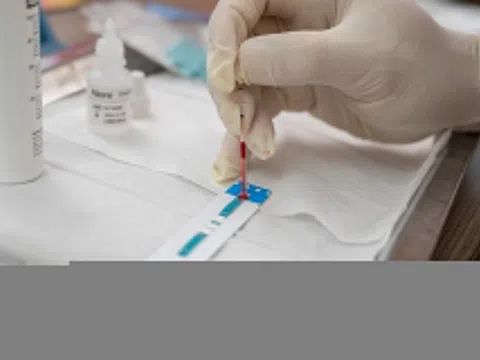

BS.CKI Tống Thị Ngọc Cầm, Phó giám đốc Y khoa miền Bắc, Hệ thống Tiêm chủng VNVC, cho biết vi khuẩn não mô cầu Neisseria meningitidis gây ra 2 thể phổ biến là viêm màng não và nhiễm khuẩn huyết hoặc kết hợp cả hai.

Khi xâm nhập vào cơ thể, vi khuẩn sản xuất độc tố đi vào máu và hệ thần kinh trung ương gây xuất huyết, tổn thương đa cơ quan. Tuy nhiên, ở giai đoạn đầu, bệnh có các triệu chứng mơ hồ, dễ nhầm lẫn với các bệnh gây viêm đường hô hấp như cảm lạnh hay nhiễm siêu vi thông thường khác, dẫn đến người bệnh nhập viện muộn, tăng nguy cơ tử vong.

Trong 8 giờ đầu, người bệnh xuất hiện triệu chứng sốt, đau đầu, đau họng, đau nhức toàn thân kèm buồn nôn, chán ăn, cáu gắt. 8 giờ tiếp theo, người bệnh rơi vào buồn ngủ, khó thở, tiêu chảy, xuất hiện tử ban, bàn tay và bàn chân lạnh, màu da bất thường kèm cứng cổ, sợ ánh sáng.

Các vết tử ban sau đó lan khắp cơ thể, gây viêm màng não kèm nhiễm trùng huyết, tăng nhanh quá trình hoại tử. Từ 16 giờ đến 24 giờ, bệnh nhân rơi vào hôn mê, co giật, mê sảng, mất ý thức. Nếu không được điều trị kịp thời, người bệnh có tỷ lệ tử vong đến 50%. 10-20% số người sống sót gặp phải các di chứng nặng nề như cắt cụt chi, điếc, liệt, chậm phát triển trí tuệ…

Tại Việt Nam, tính từ tháng 12/2024 đến nay, cả nước ghi nhận 95 ca mắc não mô cầu, trong đó có nhiều ca ở lứa tuổi thanh thiếu niên. Gần đây nhất, Hà Nội ghi nhận một bé gái 11 tuổi mắc não mô cầu khi chưa tiêm vaccine. Trước đó, một thiếu niên 14 tuổi ở Đắk Lắk mắc não mô cầu gây sốc nhiễm trùng huyết tối cấp, hoại tử chi.

Theo bác sĩ Cầm, nhóm huyết thanh A, C, Y, W nằm trong những nhóm gây bệnh phổ biến và có lưu hành ở Việt Nam. Ngoài ra, nhóm huyết thanh W và C có tỷ lệ tử vong cao.